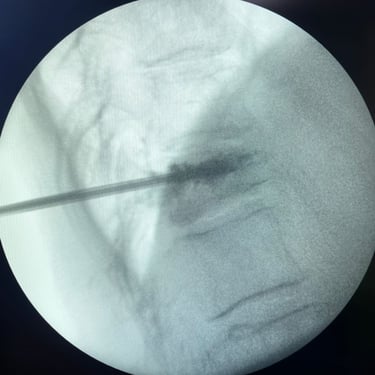

🧠 Vertebroplastia | Tratamiento de Fractura Vertebral por Osteoporosis.

La vertebroplastia alivia el dolor por fracturas vertebrales osteoporóticas mediante la inyección de cemento óseo que estabiliza la vértebra. Es un procedimiento mínimamente invasivo y seguro, que brinda mejoría inmediata del dolor y favorece la recuperación funcional.